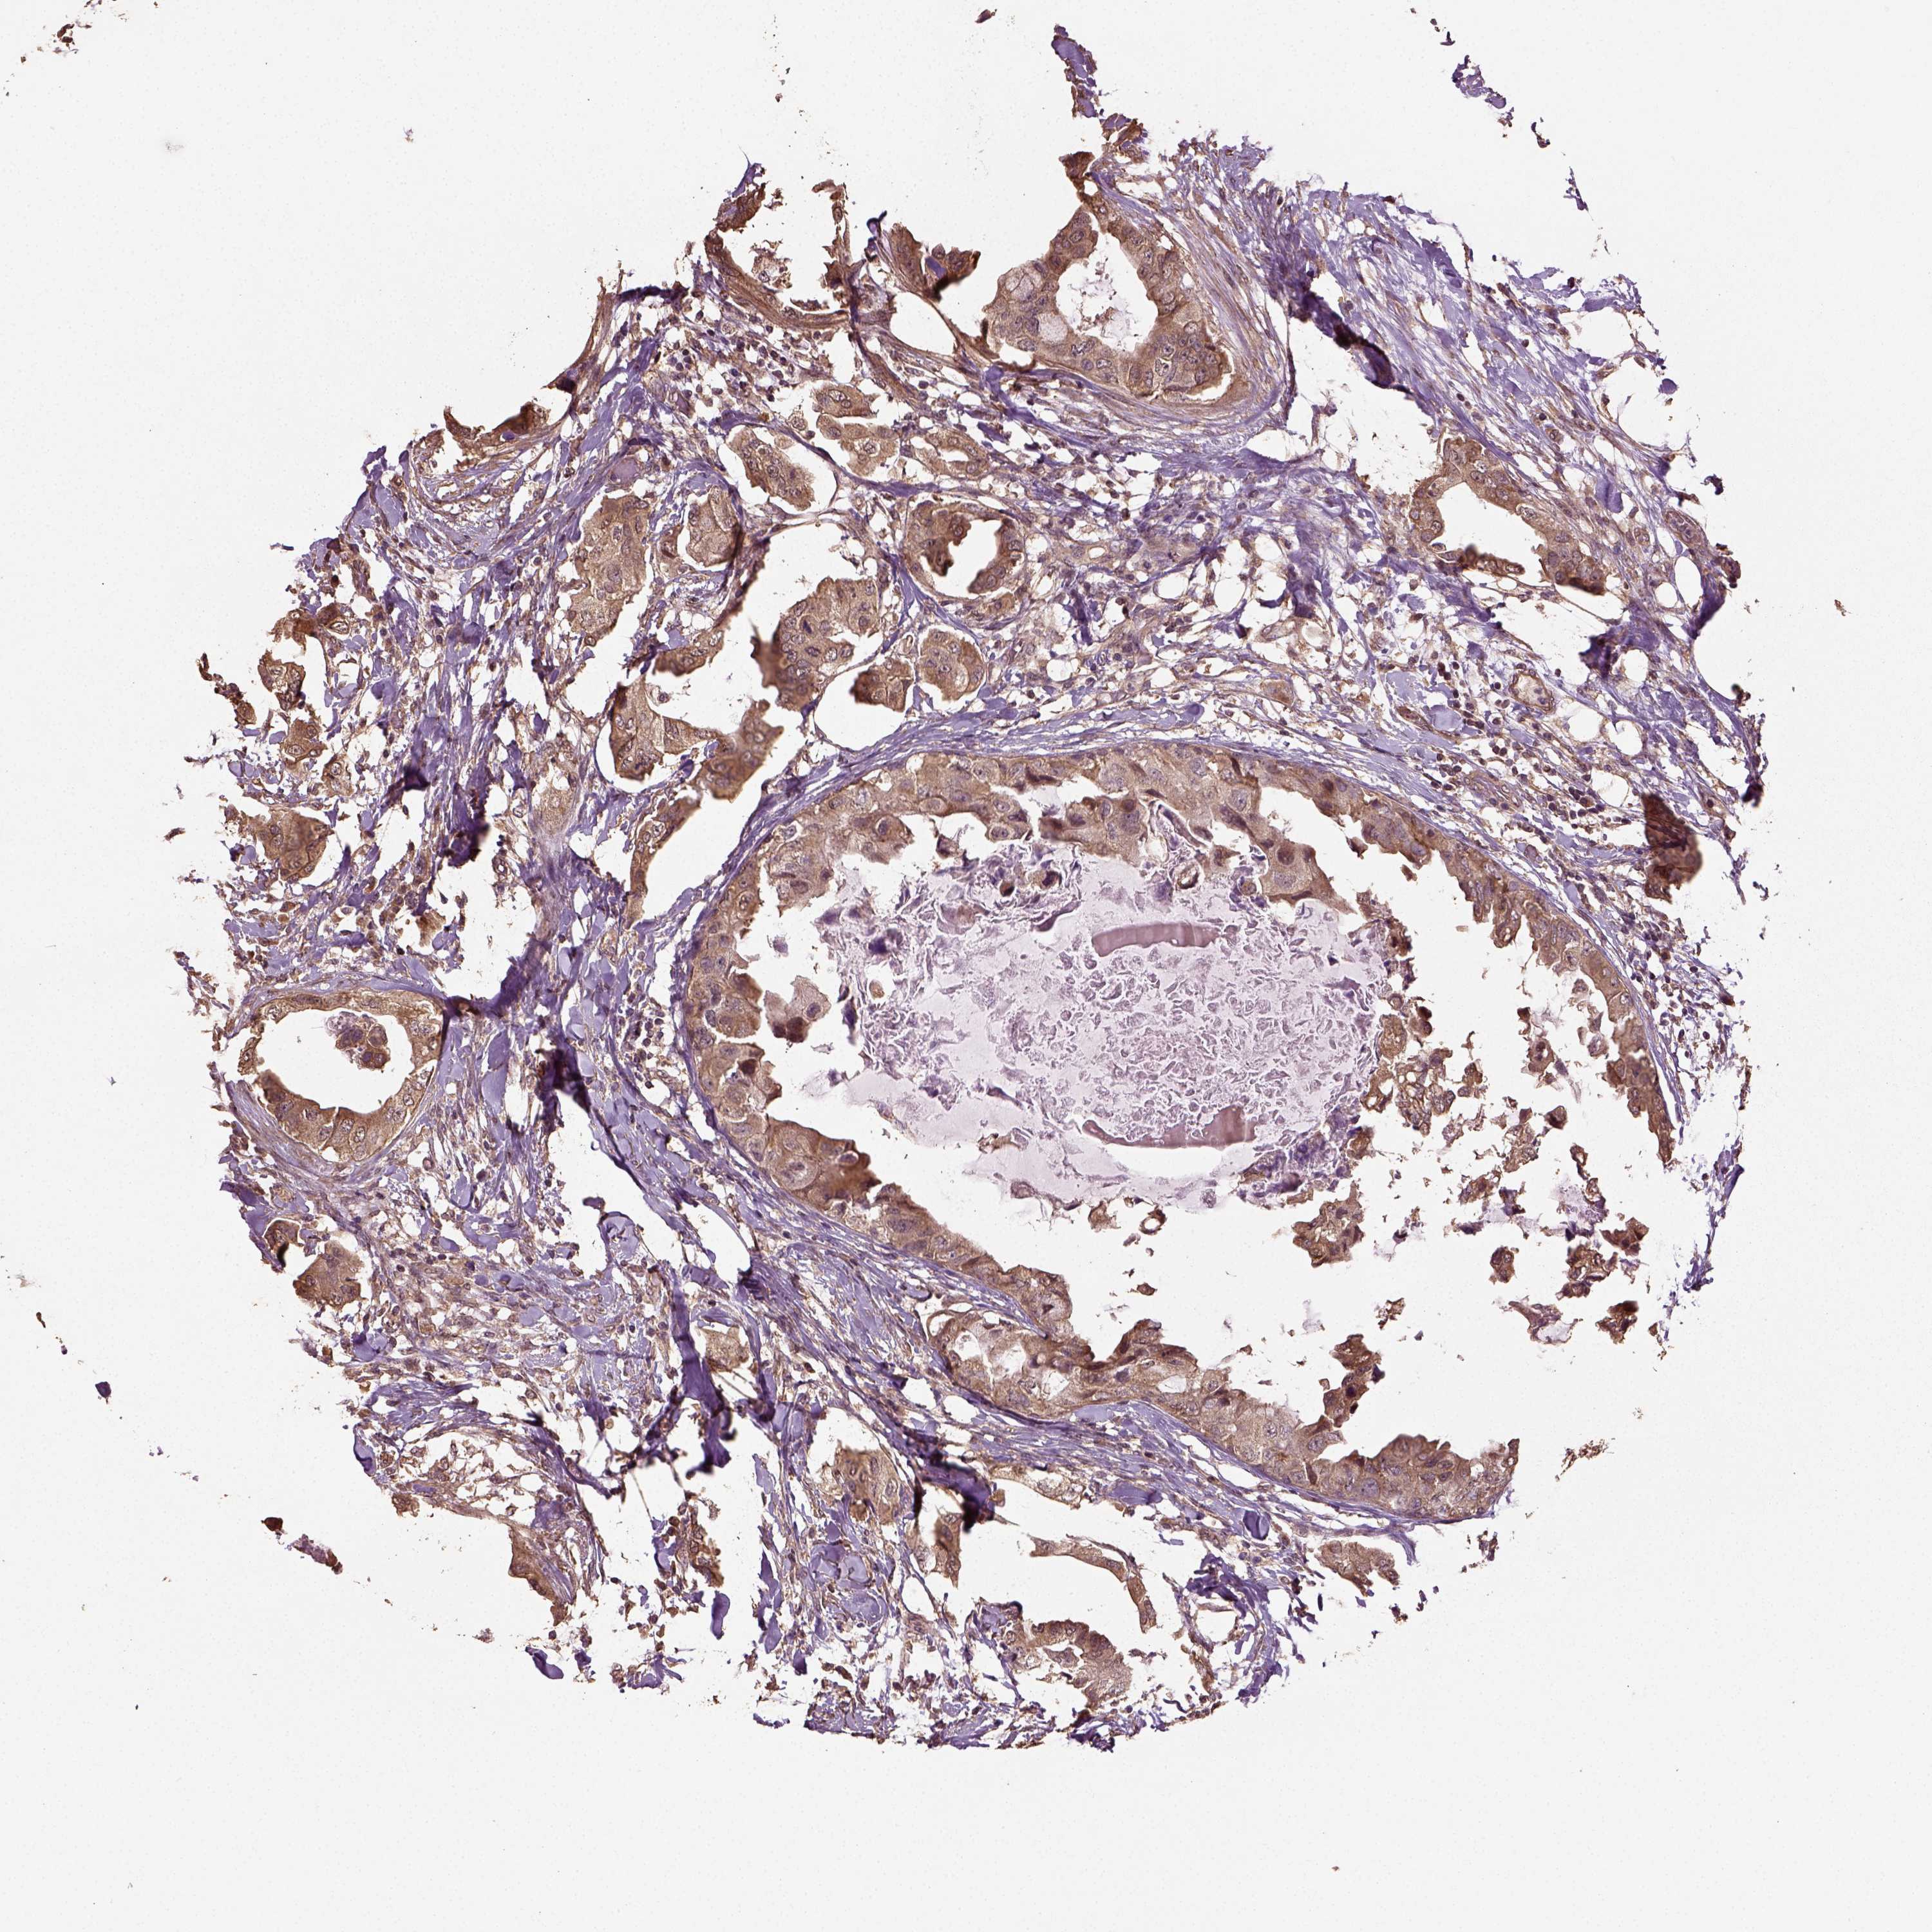

CANCER BREAST CANCER Show tissue menu

BRCA TCGA BRCA VALIDATION PROTEIN EXPRESSION